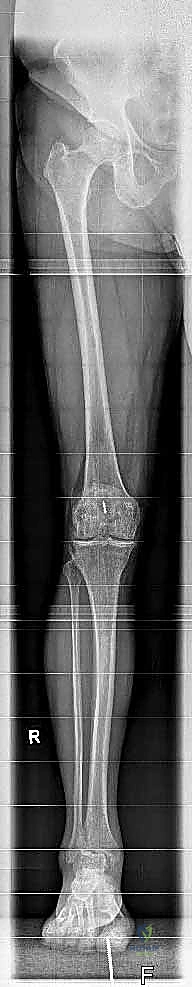

لفهم أهمية جراحة استبدال الكاحل، يجب أولاً فهم تشريح هذا المفصل المعقد. يتكون مفصل الكاحل من التقاء ثلاث عظام رئيسية:

1. عظمة الظنبوب (Tibia): وهي عظمة الساق الكبرى التي تشمل الجزء الداخلي والعلوي من الكاحل.

2. عظمة الشظية (Fibula): وهي عظمة الساق الصغرى التي تشكل الجزء الخارجي من الكاحل.

3. عظمة الكاحل (Talus): وهي العظمة السفلية التي ترتكز عليها عظام الساق وتعمل كمفصلة للحركة.

يتم إجراء فحوصات شاملة تشمل الأشعة السينية (X-rays)، والأشعة المقطعية (CT scan) لإنشاء نموذج ثلاثي الأبعاد لكاحل المريض. يساعد هذا د. هطيف في اختيار الحجم الدقيق للمفصل الصناعي وتحديد زوايا القطع بدقة متناهية.